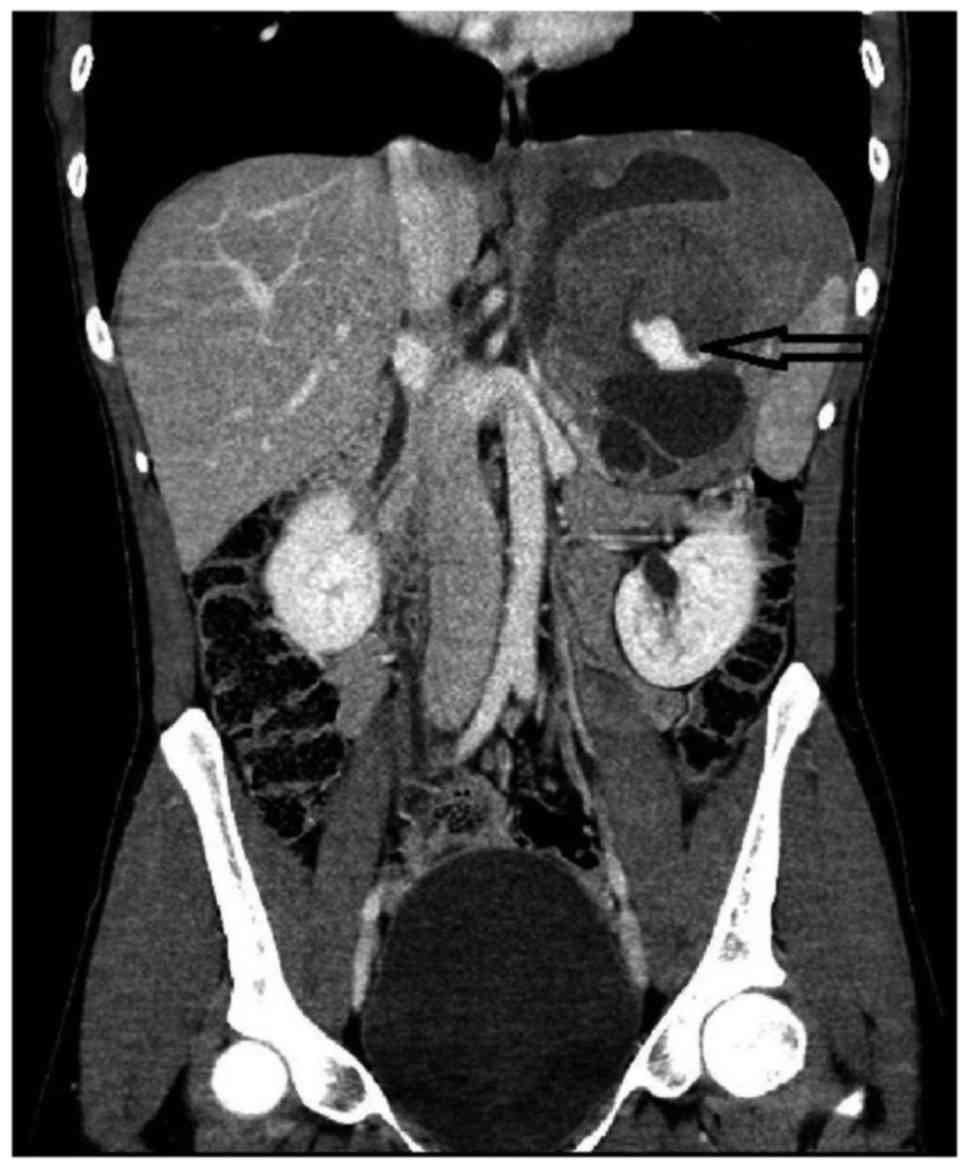

Sporadic giant intra-abdominal desmoid tumor: A radiological case report

Desmoid tumor (DT) is a locally invasive form of fibromatosis, comprising only 0.03% of all tumors. DTs occur more frequently in patients with familial adenomatous polyposis and Gardner's syndrome, as intra‑abdominal or anterior abdominal wall tumors, whereas sporadic DTs are more likely to be extra‑abdominal (only 5% of sporadic DTs are intra‑abdominal). There is also an association of DTs with prior trauma, surgery, estrogen exposure and childbirth. Imaging studies, such as computed tomography (CT) and magnetic resonance imaging (MRI) are used for preoperative diagnosis and for the planning of the surgery. Following surgery, CT and MRI are used to detect recurrence and to monitor the tumor's response to radiotherapy or medical therapy for unresectable or recurrent tumors. We herein report a rare case of a sporadic giant intra‑abdominal DT in a 28‑year‑old female patient without any predisposing factors, and highlight the importance of including DT in the differential diagnosis of huge intra‑abdominal masses.